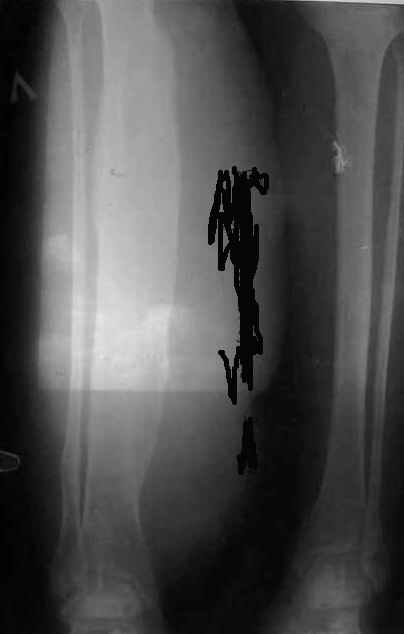

Вячеслав Дмитриевич увлек всех вопросами рентгенологии, ортопедии и проч. У меня то же кое-что есть. Кто это?

Sorry за качество снимков. Кстати, сквозь рентгенограмму просвечивает небо над исторической родиной доктора Рындина. =-O Да-да Вячеслав Дмитриевич, той самой, теперь уже далекой... А.Баулин

по такому снимку дифференциальный ряд большой будет - от юкстакортикальной саркомы до обизвествившейся поднадкостничной гематомы - хорошо бы КТ сделать - посмотреть, или растет из кортикального слоя, или просто прилежит.

Про кто это - кроме как "остеосаркома" ничего путного произнести не могу :-(

Скорее саркома Юинга.

Для саркомы Юинга характерны очаги деструкции.

Скорее всего это что-то доброкачественное.

Возможно, остеомиелит.

Я тоже подумал, что это что-то доброкачественное - надкостница видна чётко.

При саркоме наоборот.

Если я не ошибаюсь, саркома Юинга чаще бывает в молодом возрасте.

Да и выглядит немного не так.

Может фибросаркома?

Может быть синдром Паркса - Вебера?

Хорошо бы хоть несколько слов из анамнеза, давно ли это у неё? Не с детства

Если с детства, то возможна сосудистая аномалия (с-м Клиппеля Тренонне) или

что то вроде.

Остеомиелит Гарре.

По старой российской традиции предлагаю впредь называть эту болезнь не иначе как "пензенский остеомиелит Гарре"... :-)

Пензенский остемиелит Гарре - ... впервые описан профессором Афанасием Баулиным в 2005-02-22